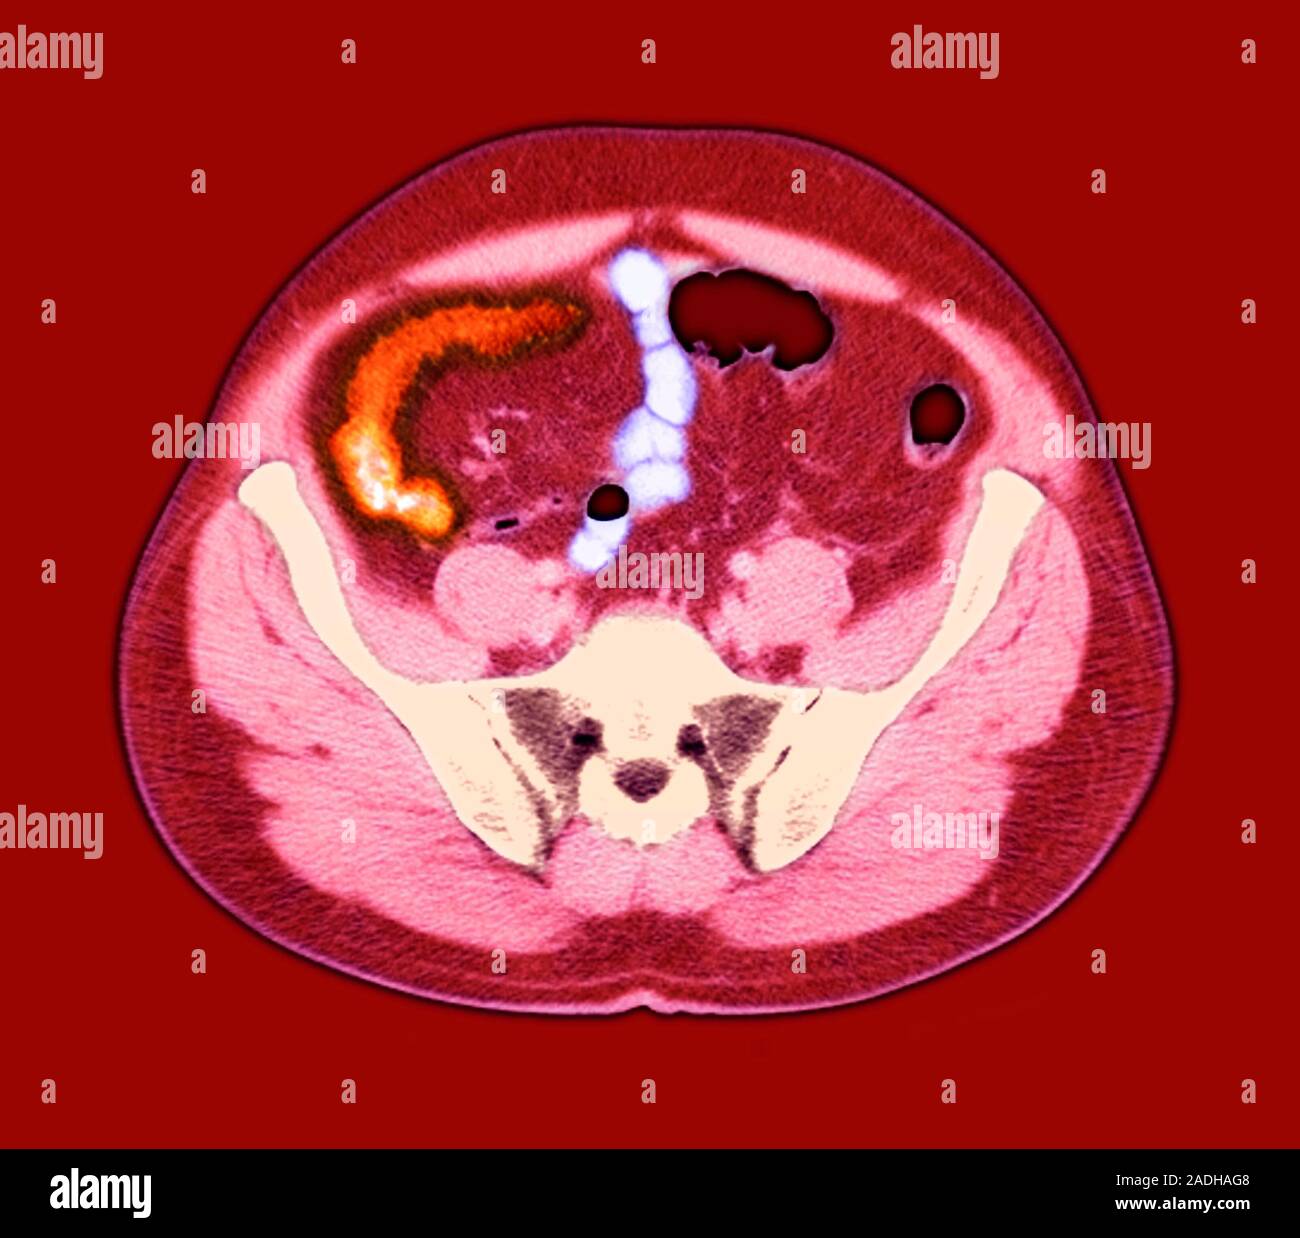

Crohn's disease. Axial coloured resonance imaging (MRI) scan Can An Mri Scan Detect Crohn Disease New and emerging roles of mri in inflammatory bowel disease. In addition, mri enterography and enteroclysis has allowed detection of small bowel crohn disease, similar to that of small bowel series, with the additional benefits of. These tests check for signs of infection, inflammation, internal bleeding, and low levels of substances such as iron, protein, or. There’s no single diagnostic. Can An Mri Scan Detect Crohn Disease.

Crohn's disease. Axial coloured resonance imaging (MRI) scan Can An Mri Scan Detect Crohn Disease You may also undergo flexible sigmoidoscopy, colonoscopy, body ct, body mri, mr enterography, upper gi, small bowel follow. If you show signs or symptoms of the condition, your doctor may use a variety. New and emerging roles of mri in inflammatory bowel disease. A systematic approach is presented to grade disease. There’s no single diagnostic test for crohn’s disease. In. Can An Mri Scan Detect Crohn Disease.